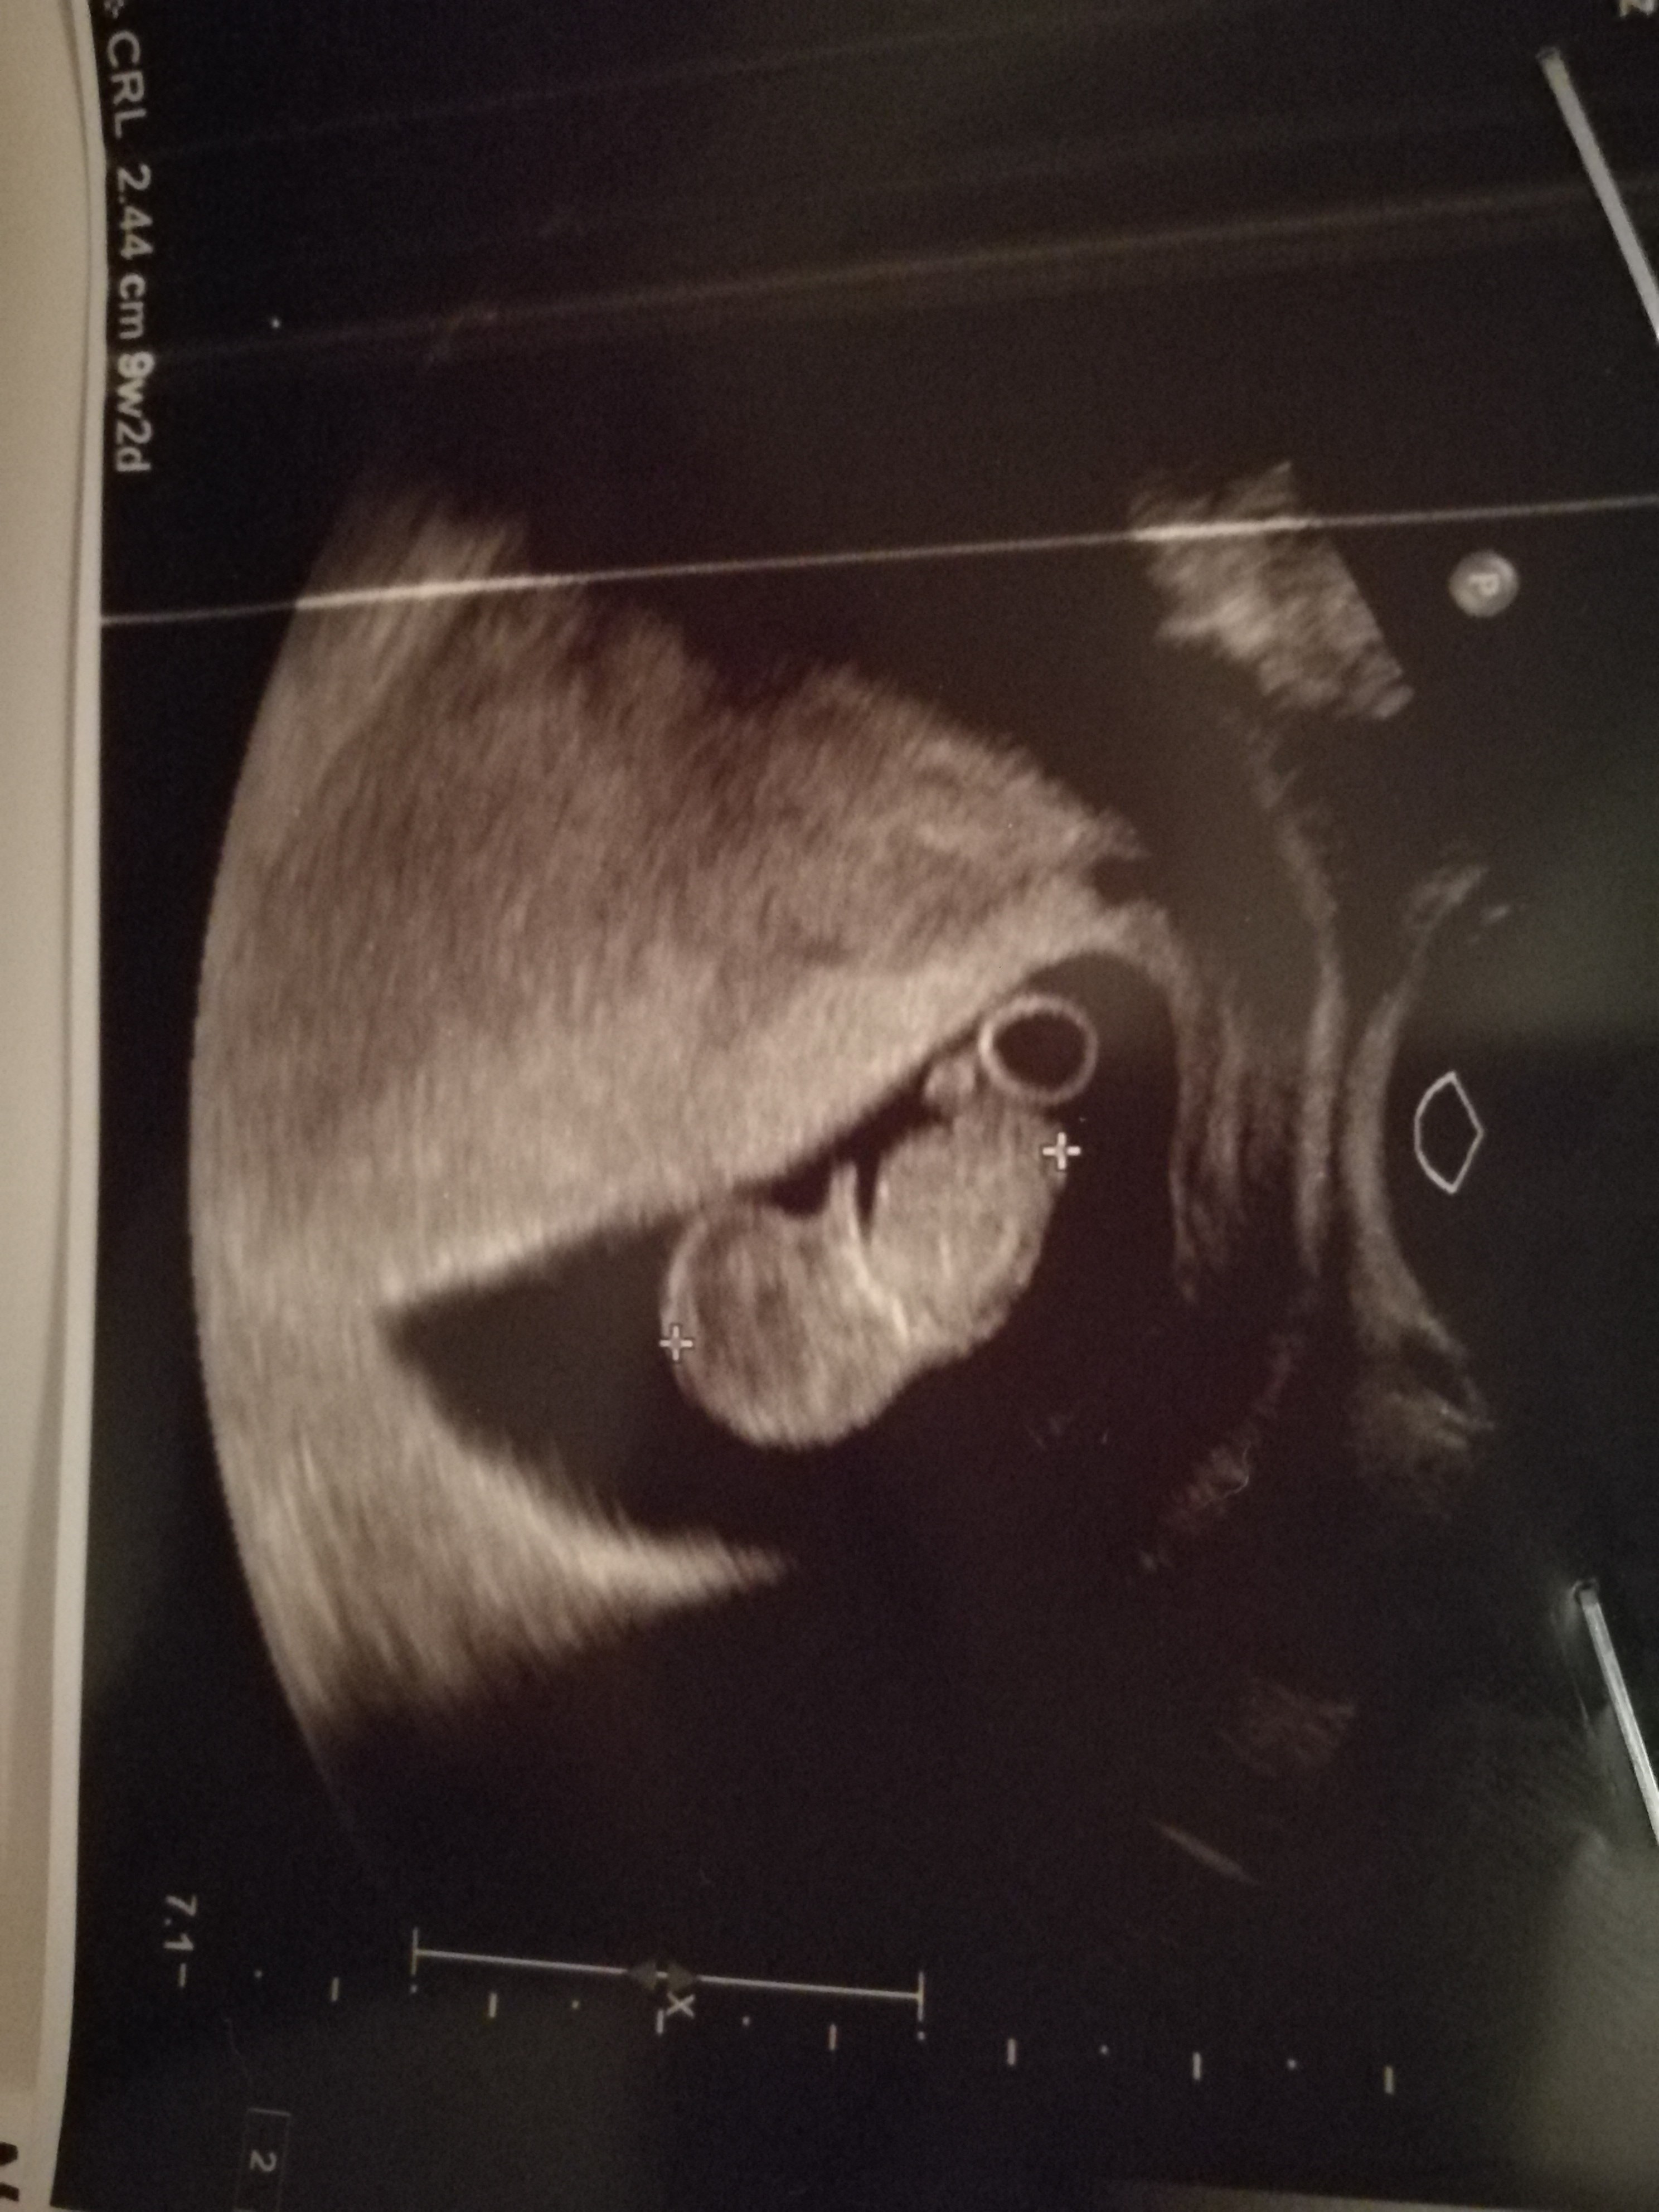

Hej dziewczyny dzis też moja wizyta i jest 9+2, termin na 8 marca :) serduszko widziałam bijące ale nie słyszalam i 2,44cm ok. 150/min :) a tak to wszystko w porządku, a obijaw prawie że nic :)

Załączniki

• IMG_20190806_223008.jpg

IMG_20190806_223008.jpg

1,2 MB · Wyświetleń: 131